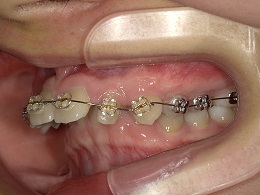

治療中左側

治療中上顎